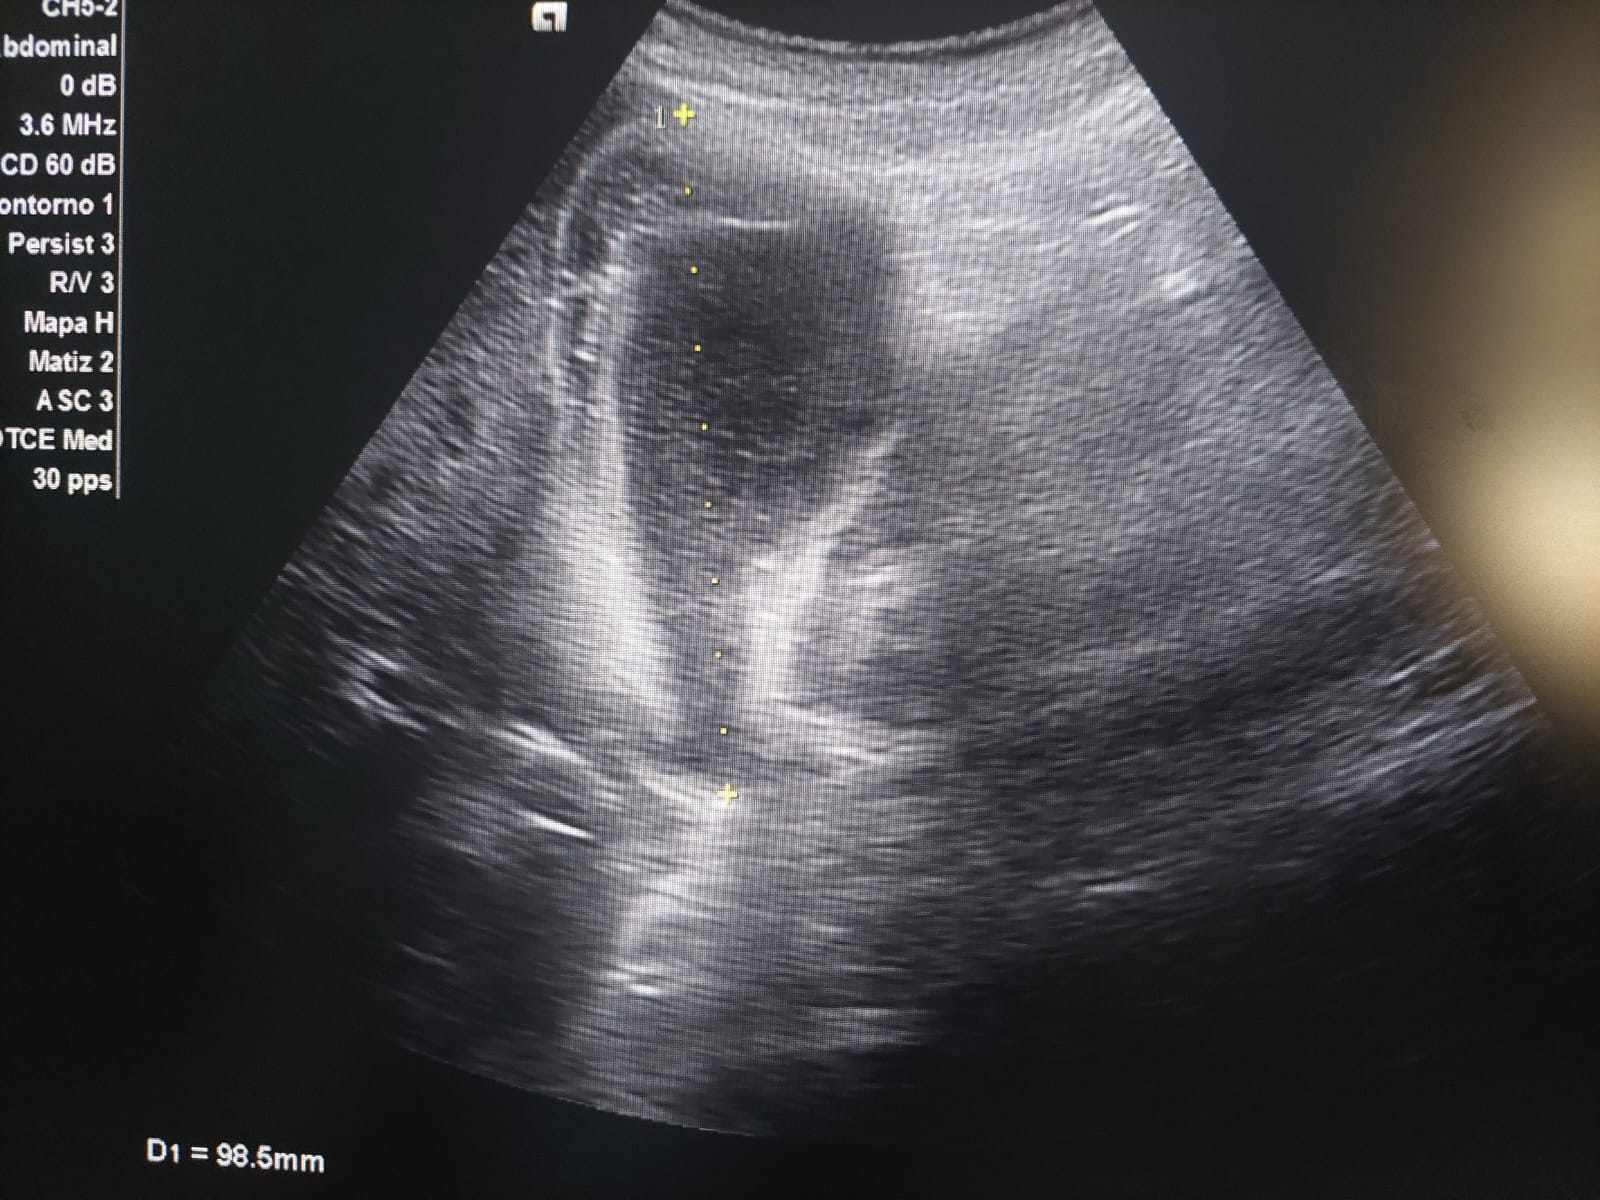

Se realiza una ecografía clínica abdominal en la que destaca un engrosamiento de la pared anterior de la vesícula biliar, sin imágenes hiperecogénicas en su interior. Parénquima hepático y riñón derecho con morfología y ecoestructura normal.

Se deriva a cirugía que solicita ecografía reglada informándola como vesícula biliar distendida, con engrosamiento marcado y limitado a la pared del fundus vesicular asociado a barro biliar. Hallazgos no concluyentes para colecistitis aguda, y podría estar en relación con adenomiomatosis del fundus asociado a barro biliar, o menos probable colecistitis subaguda.